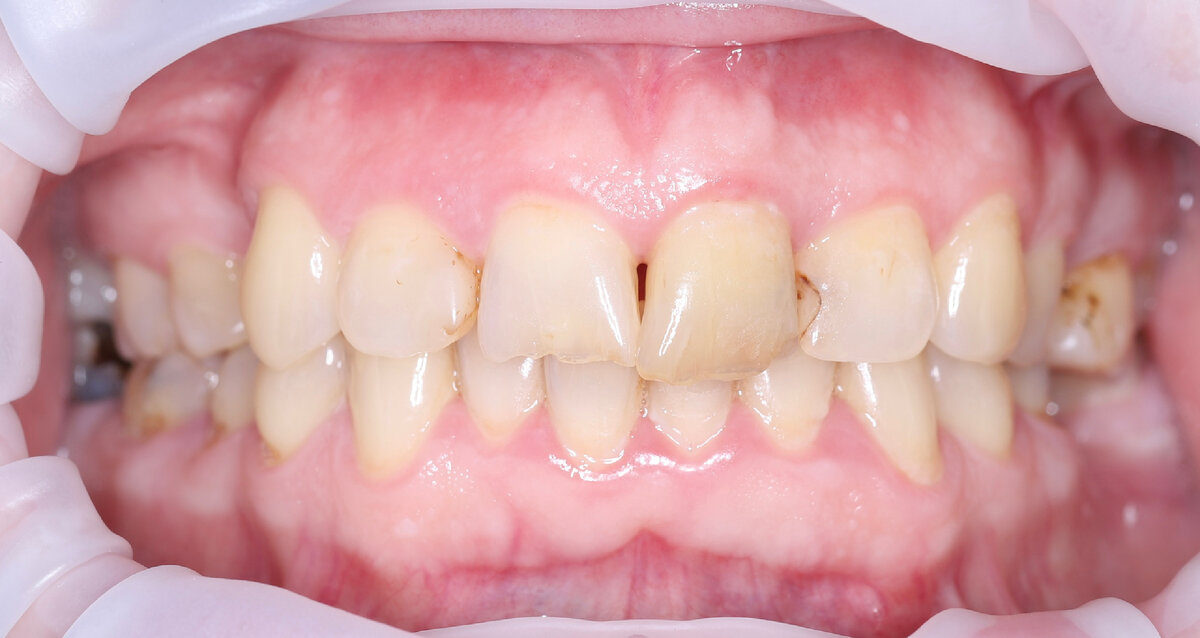

После выявления жалоб и визуального осмотра я сделал фотопротокол. Для того, чтобы мы вместе сели возле монитора и наглядно всё посмотрели и разобрали детально.

Чтобы настало общее понимание накопившихся проблем и способов их решения.

Что я увидел в полости рта?

Старые пломбы, с нарушением прилегания и развитием вторничного кариеса под ними: